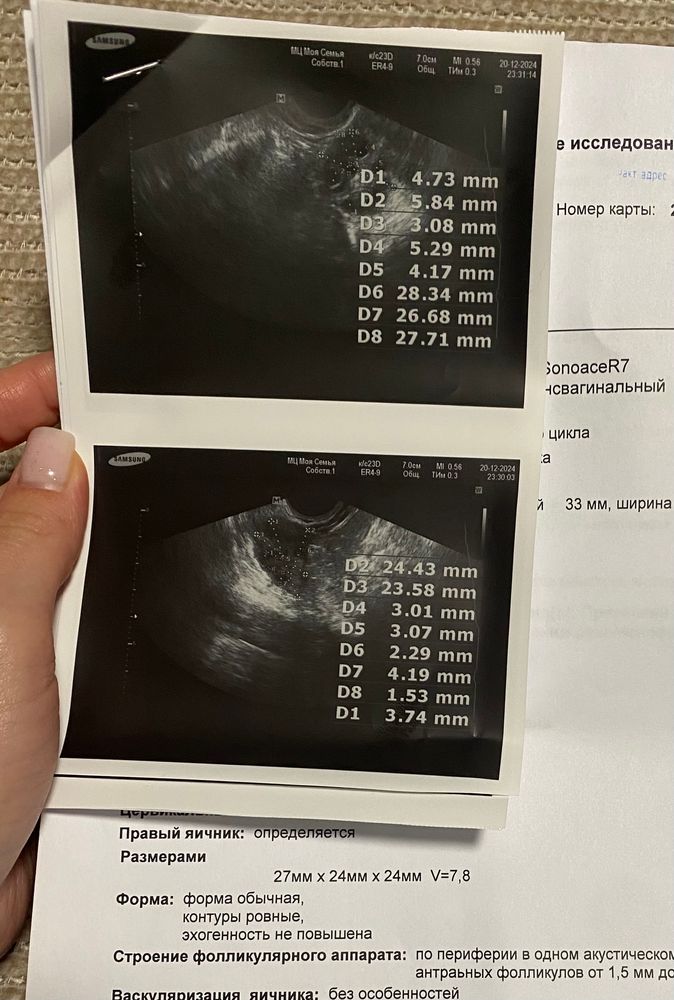

Виктория , редко. Последний год были +- регулярные М. Но не знаю, О была или нет, не отслеживала. Вот как назло как начали планировать Б, такая сильная задержка (19 дней), и цикл без овуляции. Узист напугала, что месячных могу не ждать, эндик слишком мал. Хотя я думала, что бывают циклы без О, но М потом сами и приходят.

Тат'яна, а мес сами приходили в итоге всегда? Не вызывали? Переживаю теперь, что месячные вообще не придут.. мне сказали они приходят от эндика 12, а у меня 5,3